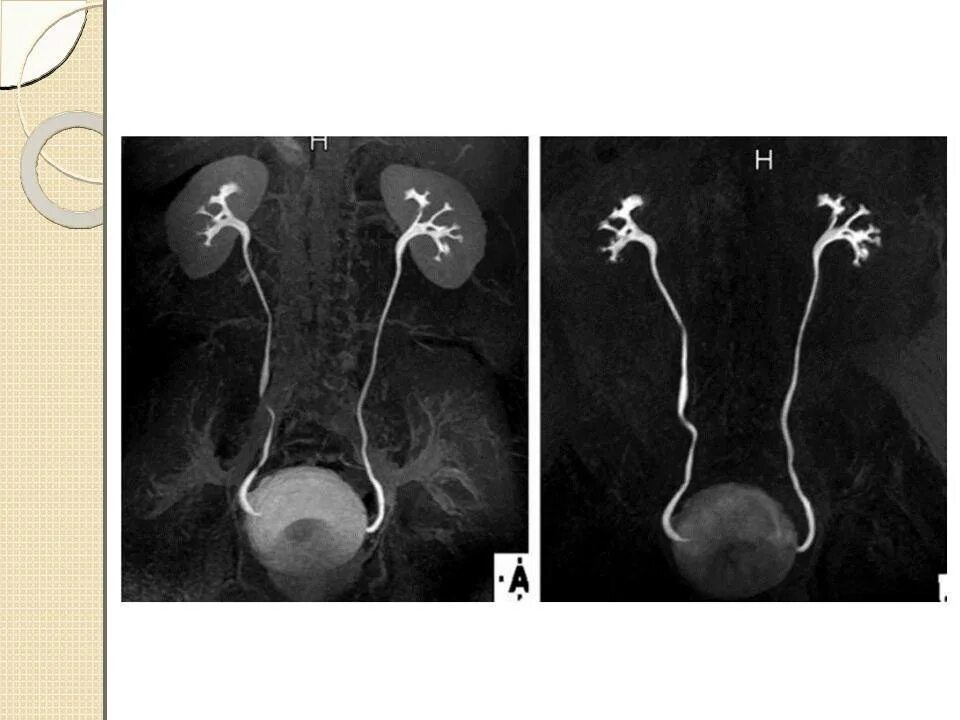

Как делается урография